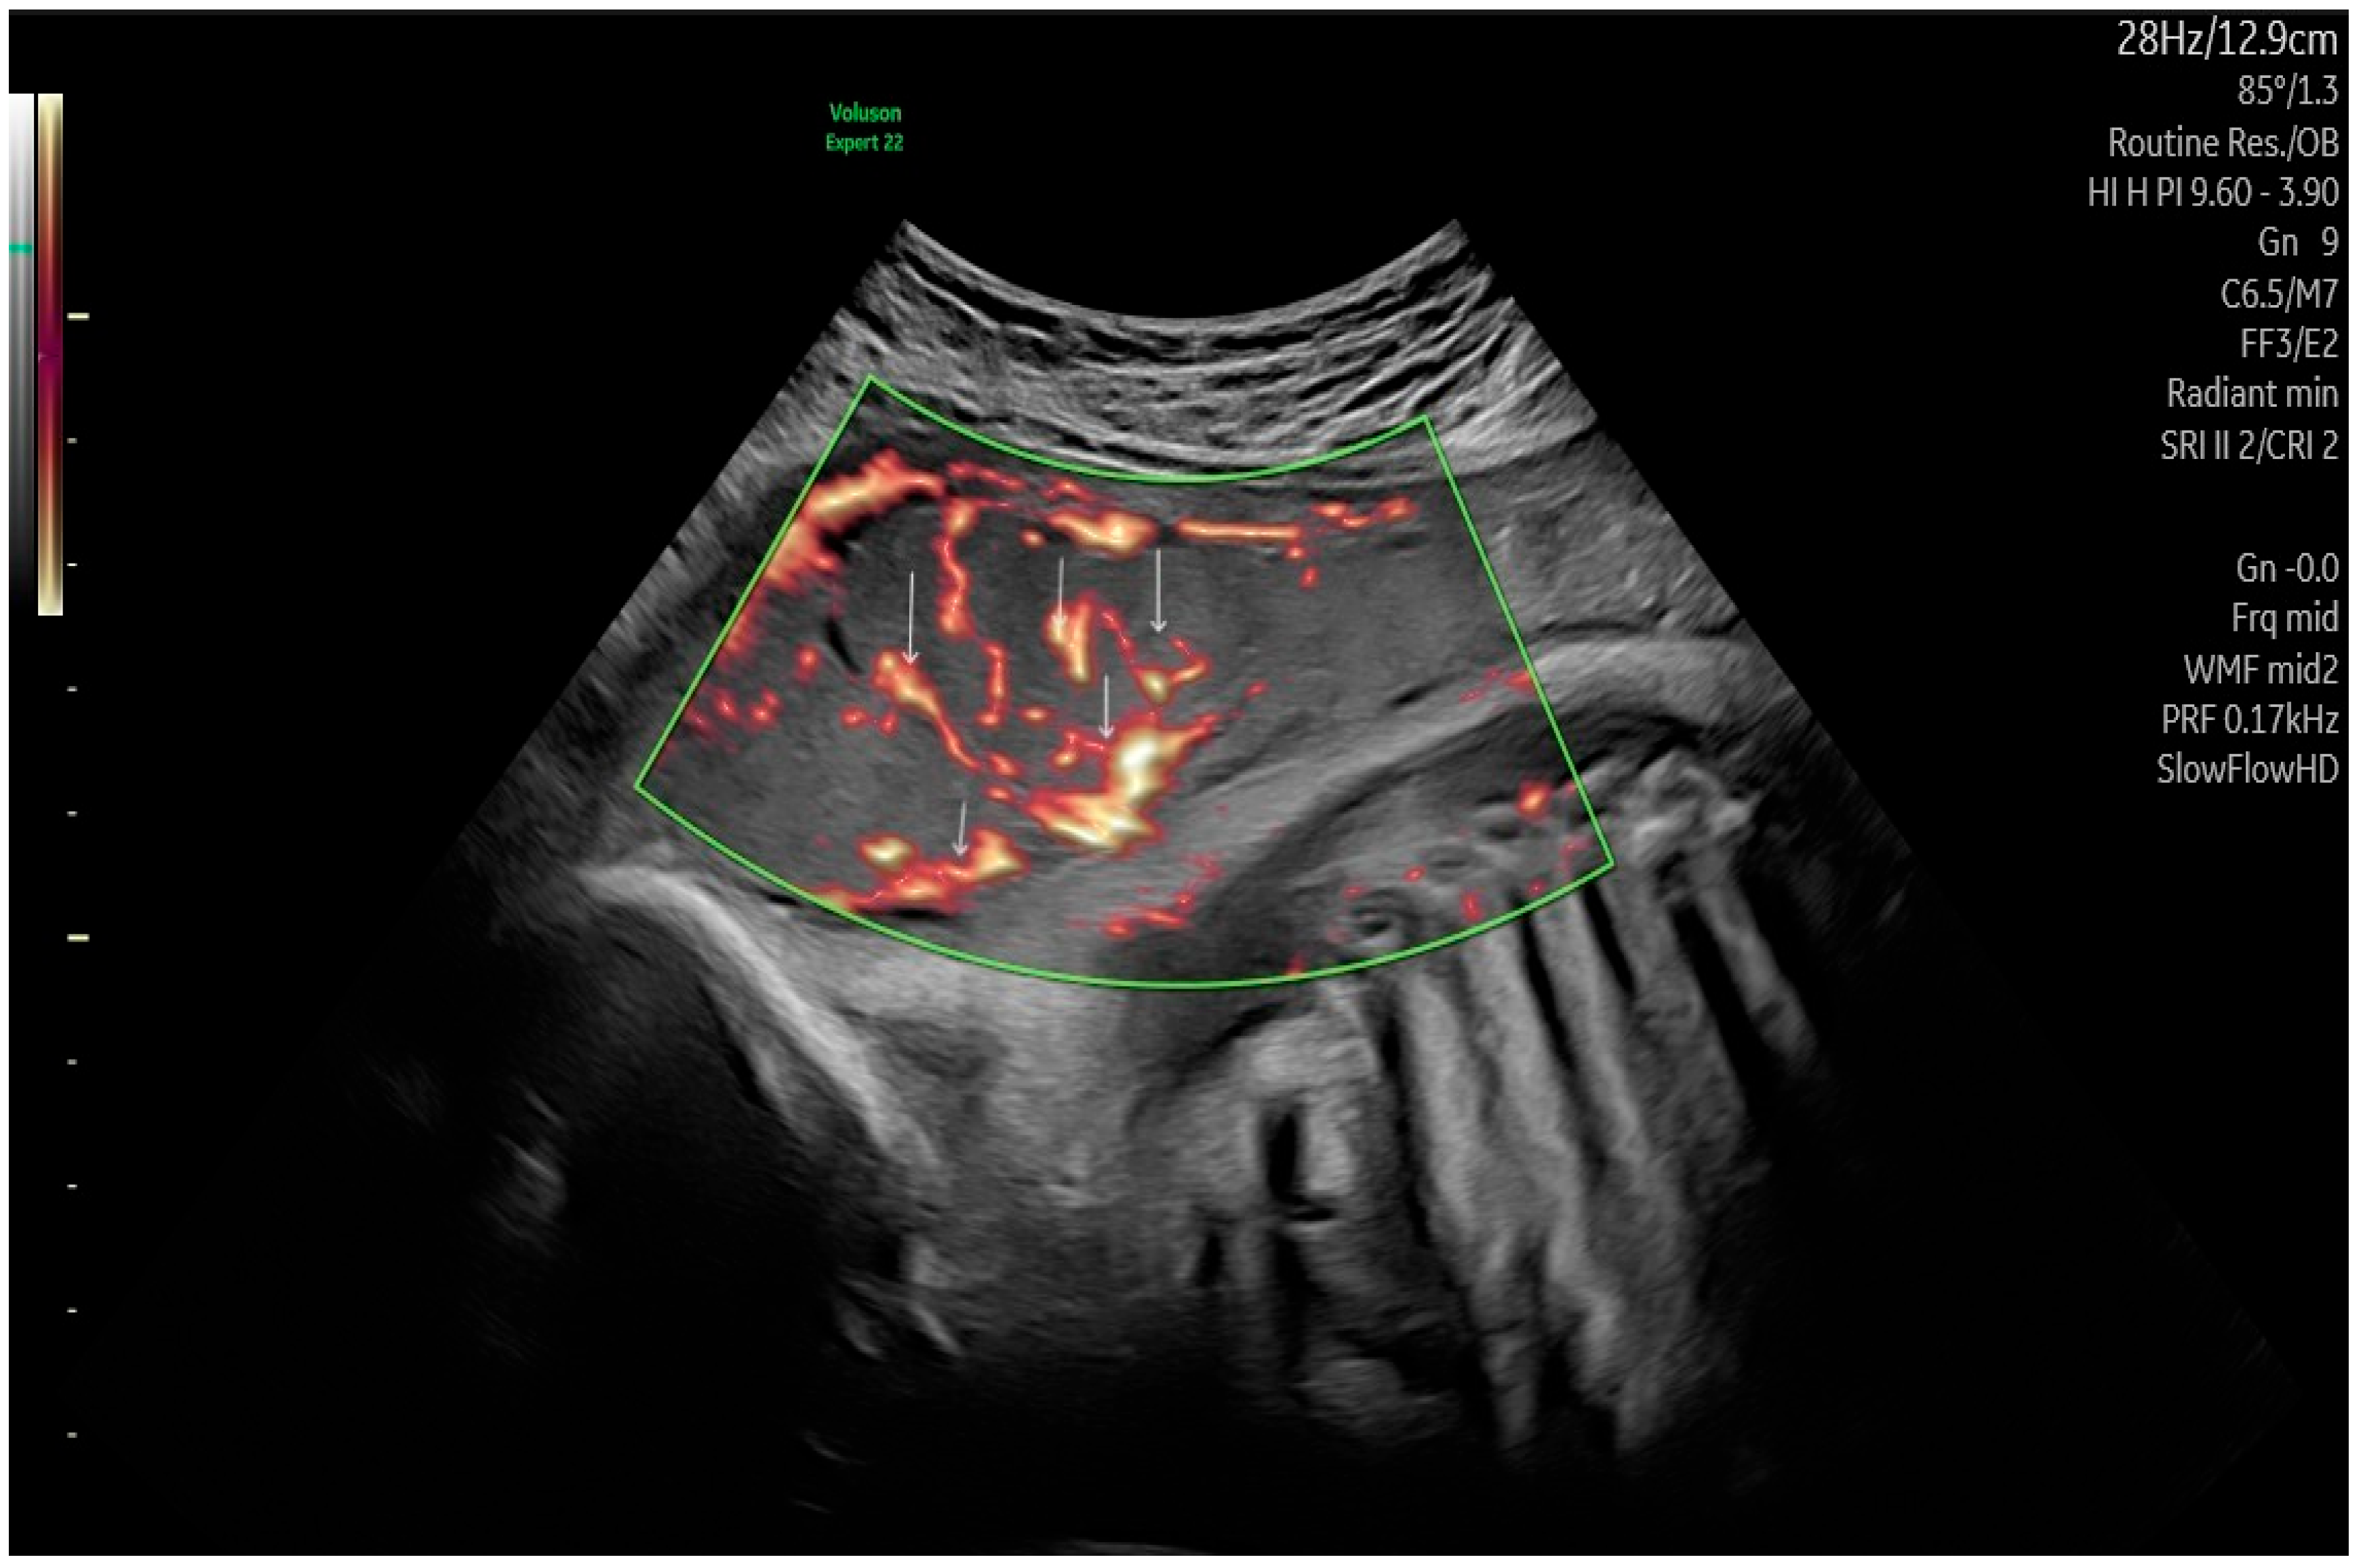

Table 2 exhibits the values of the placental perfusion using the three-dimensional power Doppler indices. The placental volumetry was prepared in 3-D mode by the VOCAL program (Figure 1). The in vivo vascular measurements were performed immediately below the umbilical insertion, which is the most densely vascularized part of the placenta (Figure 2). The obese and GDM participants expressed significant differences in terms of the sonographic placental parameters. The placental volume was significantly elevated, while the vascularization indices (VI: vascularization index, FI: flow index, and VFI: vascularization flow index) were significantly depressed compared with normal-weighted pregnant women. There were no significant alterations in placental volume and 3-D PD indices between the obese and GDM cases.

Figure 2. Placental vessel using three-dimensional power Doppler (3-DPD) mode, which facilitates the visualization of vessels (red lines) with a low diameter (↓) with a relatively low-grade velocity blood flow (in the green box).